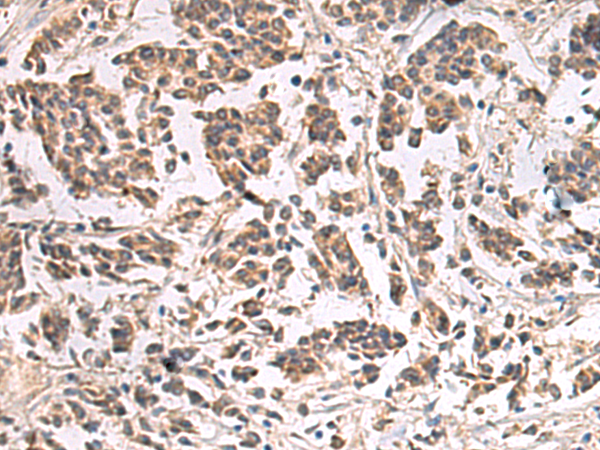

分类: 科研抗体货号: P06577别名: PIF79; GMEB-2; P79PIF应用: IHC反应种属: Human, Mouse, Rat